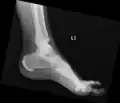

Ectopic calcification and new bone formation in diffuse idiopathic skeletal hyperostosis (DISH) -